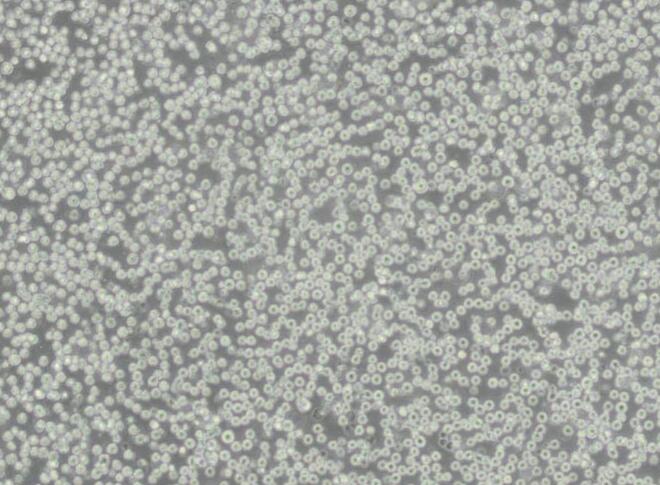

SK-BR-3人乳腺癌细胞

- SK-BR-3人乳腺癌细胞

- 1*10^6/T25

- 细胞 细胞系